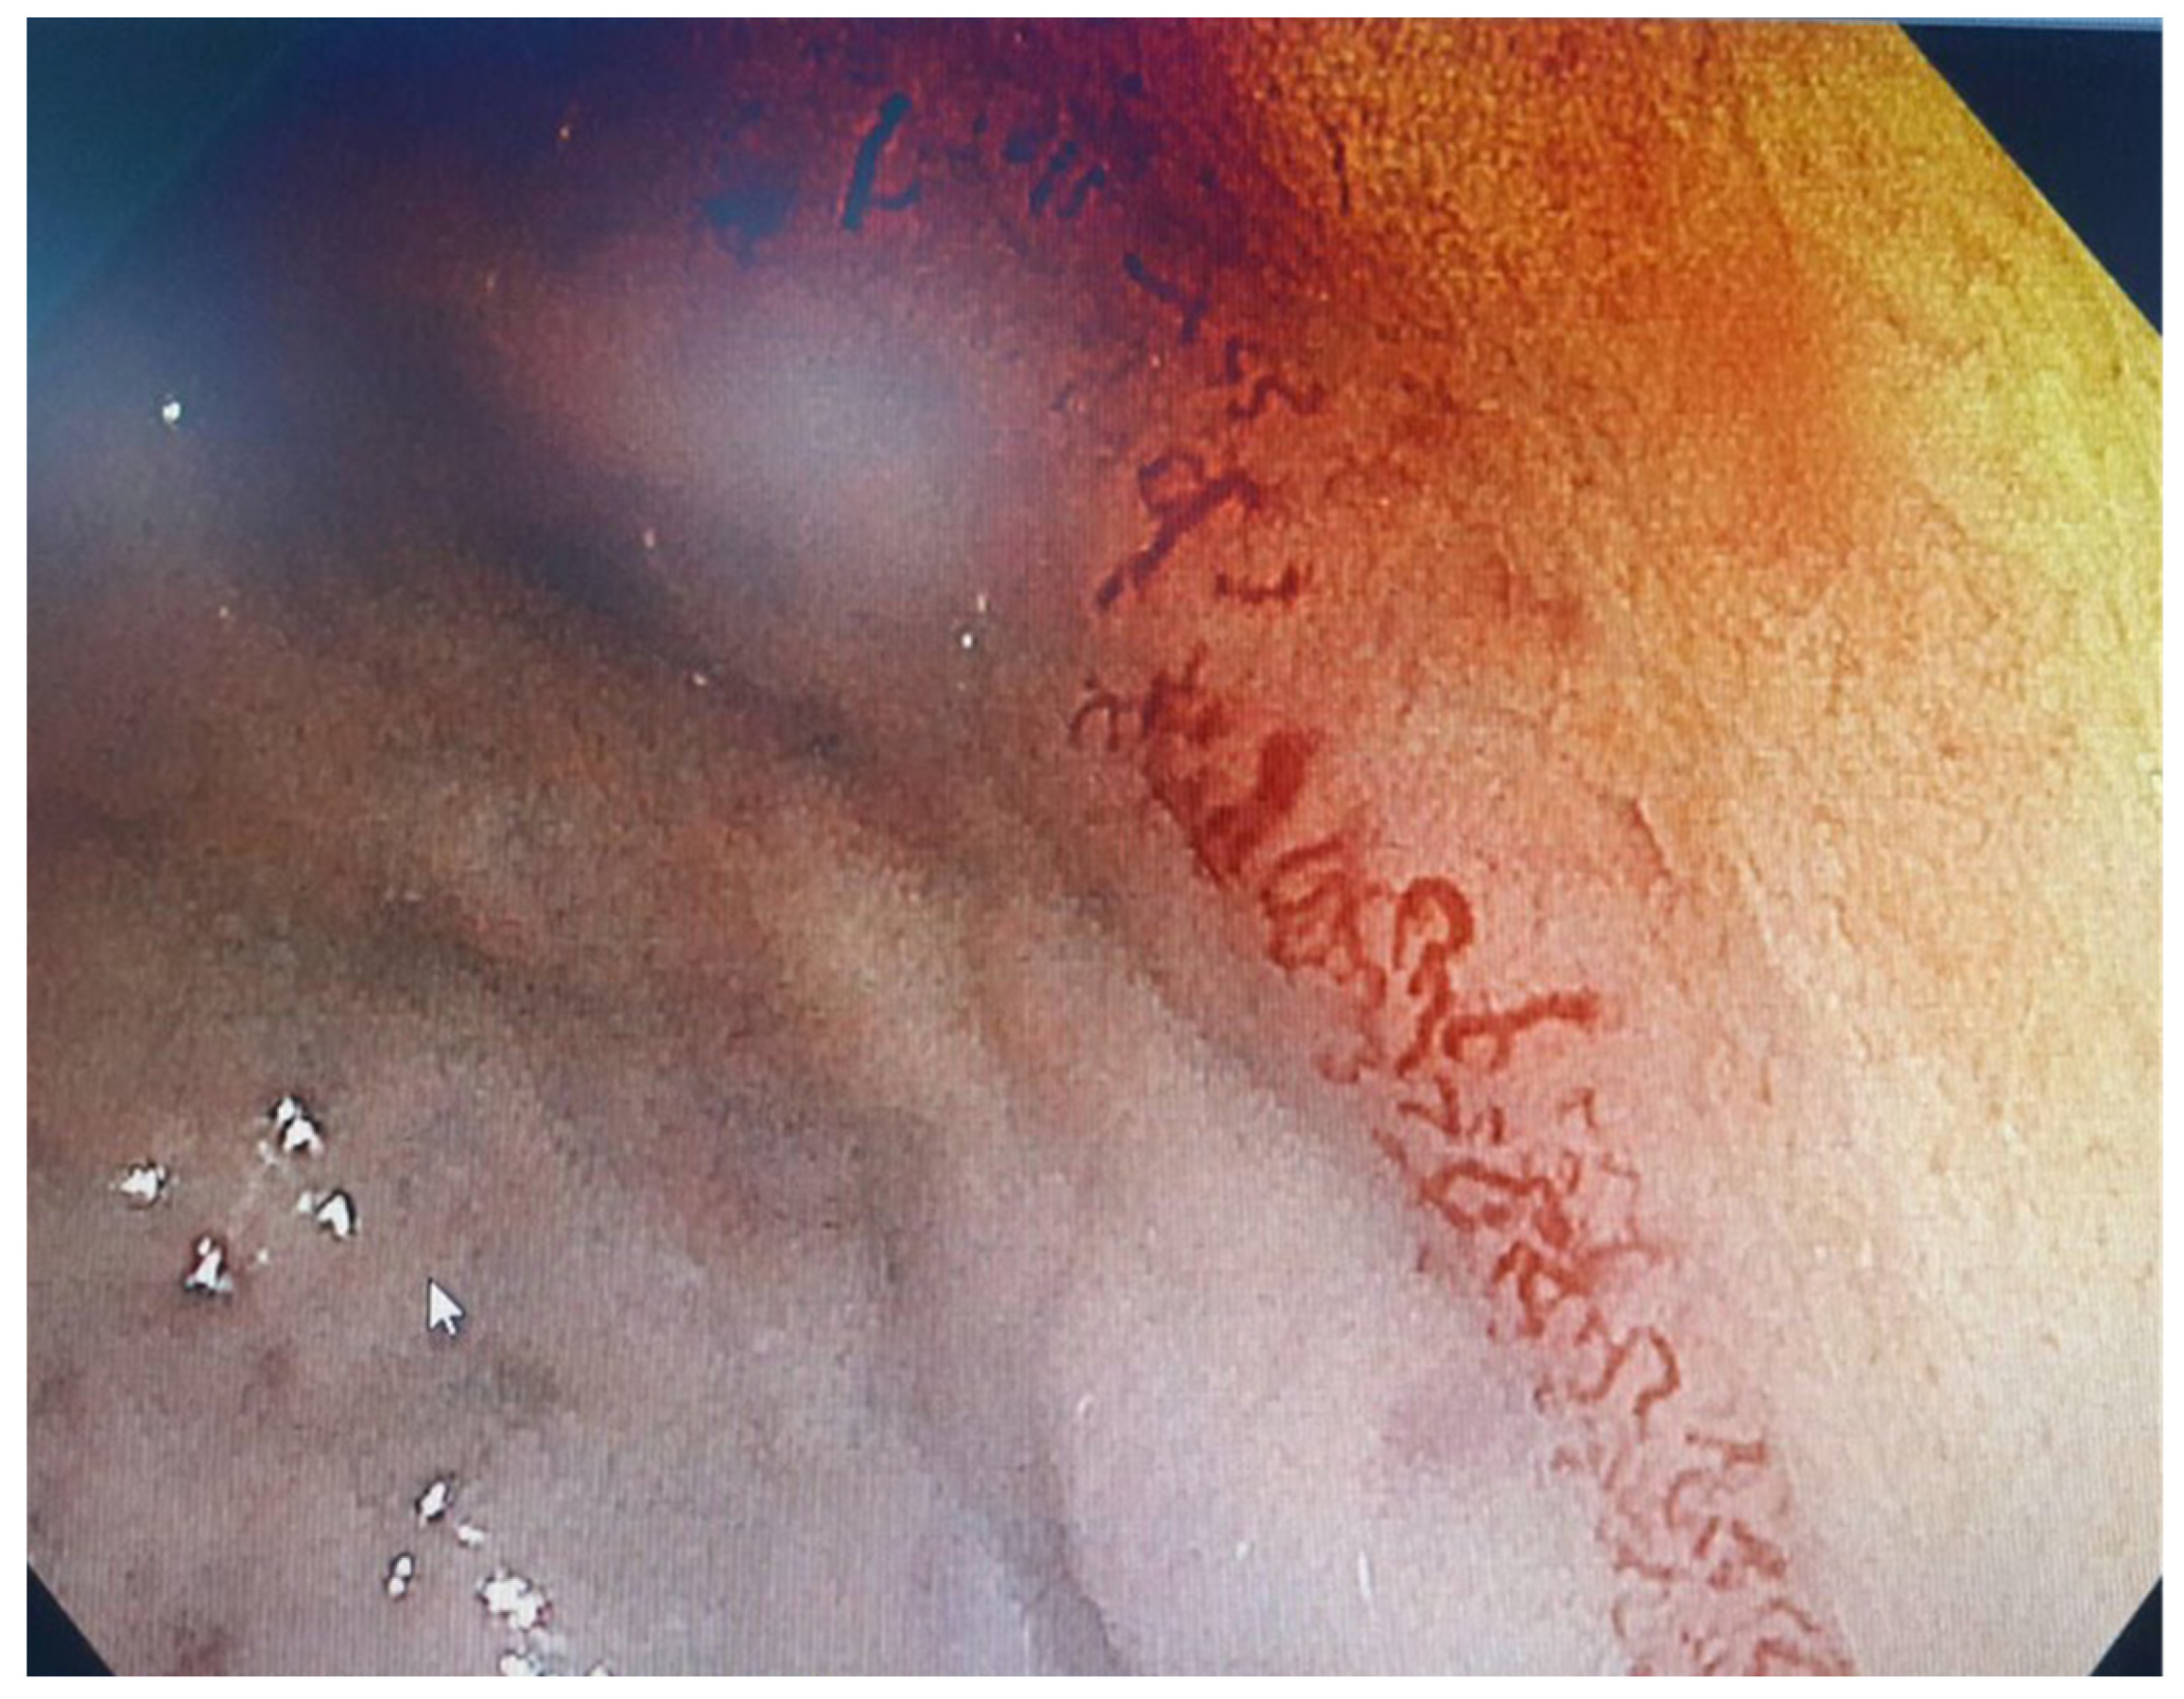

2. Case Report